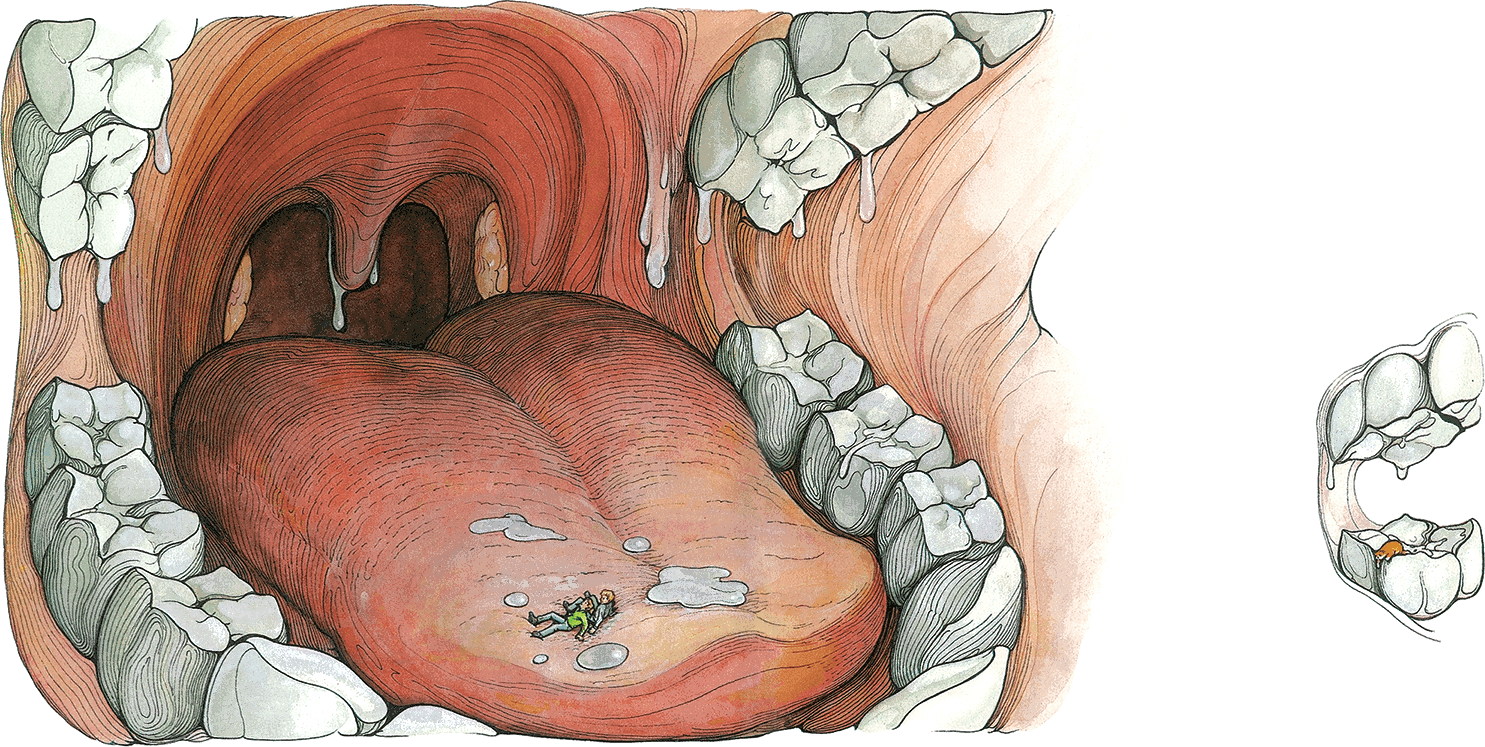

Под потолком висели огромные зубы. С них медленно сползала поблескивающая влага и по розовым стенкам стекала на мягкий бугристый пол.

– По-моему, – чуть слышно шепнула Молли, – нас ест… великан.

– Ну, а это тогда что? – Молли указала на гигантский торчащий из пола зуб. Вдруг этот зуб испустил ноющий звук. Близнецы окаменели от ужаса. – Может, он больной? – ахнула Молли, но тут на зуб влезло нечто мокрое, несчастное и апельсиновое. Вновь раздалось страдальческое «мяу!».

– Быстрее! – Молли кое-как поднялась на ноги. – Вода прибывает.

Они ухватились друг за друга и попробовали идти по бугристой пружинящей поверхности.

– Это великаний язык, – объявил Макс. – И мокро тут не от воды, а от слюны!

Они добрались до Бакстера и стащили его вниз как раз вовремя: верхние и нижние зубы сомкнулись с чудовищным стуком и началось землетрясение. Язык приподнялся, изогнулся, и они соскользнули в глубину рта. Там их бросило через водопад, как они ни цеплялись за скользкие стены. Язык величественно замер, потом его изогнутый конец начал опускаться к нижним зубам, но детей и кота уже несло в противоположную сторону.

– Держись! – крикнул Макс. – Нас глотают!

Тут прямо под собой они увидели довольно широкий уступ, спрыгнули, уцепились за него и с ужасом наблюдали, как струя водопада катится над ними в бездонную черную пропасть.

– Мы в ловушке! – Молли посмотрела вверх. – Назад нам ни за что не влезть. Стены слишком крутые и скользкие. – Она поглядела вниз. – И спуститься мы не можем. Разобьемся насмерть. У Бакстера, правда, когти… Может, он сумел зацепиться за стенку.

– А мы так не умеем. Значит, мы в ловушке, – закончила она уныло. – Внутри великана.

– Тогда это надгортанник, – сообщил Макс. – Я видел его в книге. Он предохраняет дыхательное горло, то есть трахею, когда мы глотаем, – чтобы пища не попала в легкие и мы не подавились.

– Туда Бакстер и провалился, – сказала Молли. – На вдохе. Значит, второй туннель для пищи. – Она указала на пропасть, в которую обрушился водопад.

– Да, это пищевод, – согласился Макс, но от того, что они теперь знали, где находятся, им ничуть не стало легче. – Только не паникуй. Мы должны сохранять хладнокровие. Не терять головы… Собраться с мыслями.

Они посмотрели вниз на два огромных зияющих отверстия, а потом вверх, туда, где по стенкам гигантской глотки стекала слюна.